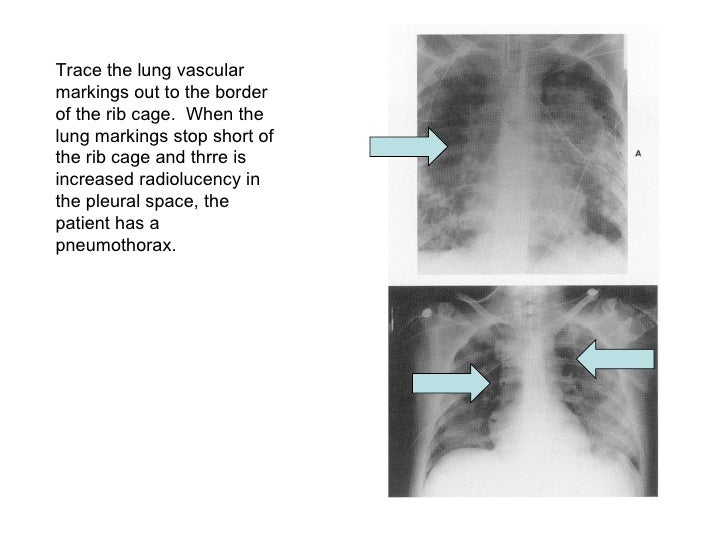

Pneumothorax Chest XRay MedSchool